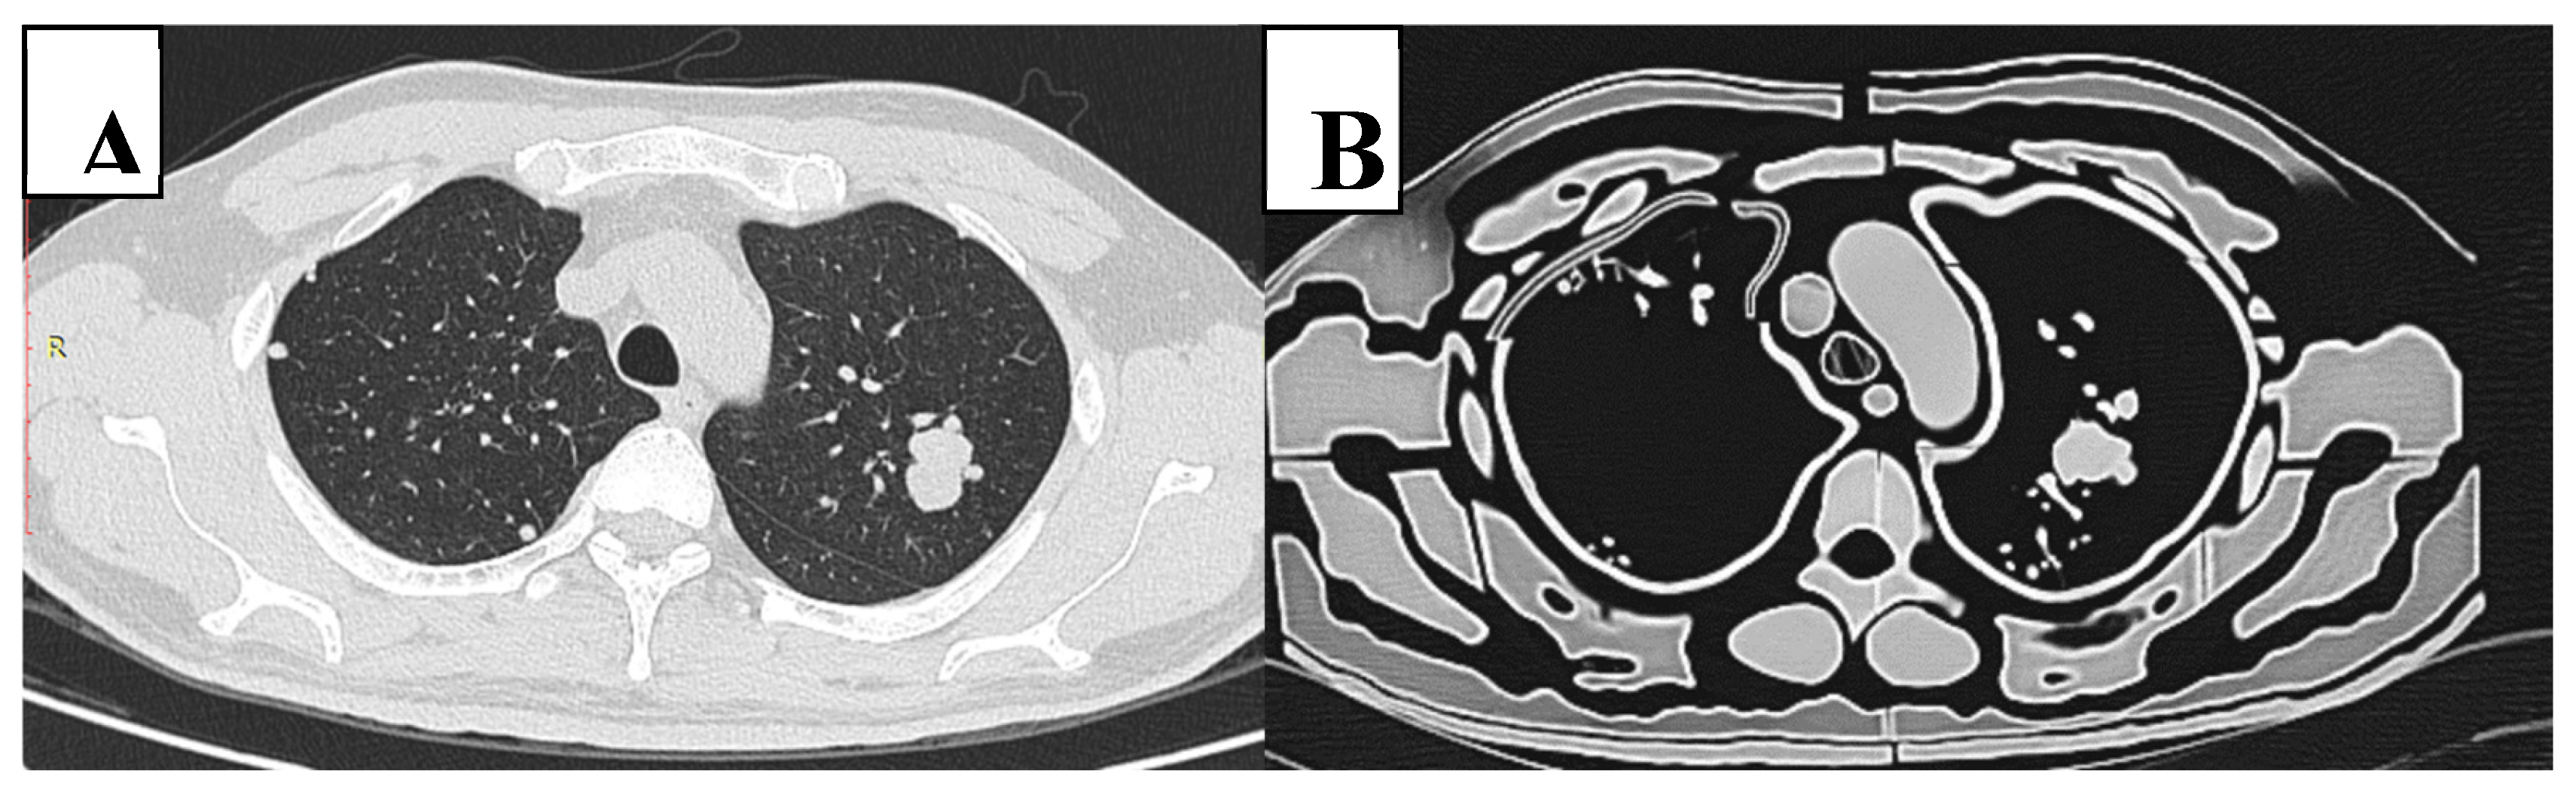

Figure 6. CT slice of original patient image (A) compared to the phantom image (B). Similar morphological appearance of phantom and patient scans is evident. However, in the phantom, the smaller pulmonary vessels and lung interstitium are absent and air gaps exist between tissue layers. Edge enhancement surrounding structures is also evident within the phantom scan.

Figure 4 and Figure 5 showcase the 3D-printed chest phantom, while Figure 6 presents a comparative CT slice of the phantom alongside that of the patient. Table 3 presents HU measured for each of the printed thoracic tissues compared to those of the patient. The complete phantom weighed 22 kg.

Manipulating infill percentages is a useful method that researchers employ to control HU in FDM printing due to the linear relationship between infill percentage and HU (Figure 2) [45,51]. However, this method has been criticised for creating unrealistic texture materials with microscopic or macroscopic voids that leads to high deviations in attenuations, which may underlie the variations in HU reported for the same 3D printing filaments between publications [47]. Consequently, the air gaps present may contribute to the low Hounsfield Units achieved for some of the tissues measured in this study and the large variations of HU relative to the patient (Figure 7) [48]. Modifying infill percentages also creates solid shell artifacts visible at boundaries of materials [50], which possibly enhanced contrast and visibility of the lung nodules in this study (Figure 6).

This study reveals that a low dose CT protocol of 80 kVp, 30 mAs with ADMIRE 3 (0.23 mSv effective dose), is a potentially viable option for good diagnostic ability of lung nodules on CT scans. These findings are in agreement with Leitão et al.’s study that concluded that 80 kVp, 30 mAs (0.072 mSv) provides sufficient diagnostic capability for detection of lung nodules in an Alderson Rando phantom [13]. However, our study provides more weight to these findings due to the incorporation of pulmonary vessels that are absent from commercial phantoms. Nevertheless, the relatively high contrast of nodules to lung background is still considered a limitation of this study due to the inability to reproduce the smaller peripheral lung vessels (Figure 6). Thus, there appears less “anatomical noise” within the constructed phantom compared to the patient. The small branched peripheral vessels were not able to be printed due to limitations of the resin material. The flexible and flimsy material could not withstand the pressures of the printing process and forces involved from removing the support material. Future studies can use more robust material or alternatively, use traditional moulding techniques to create the lung vessels.